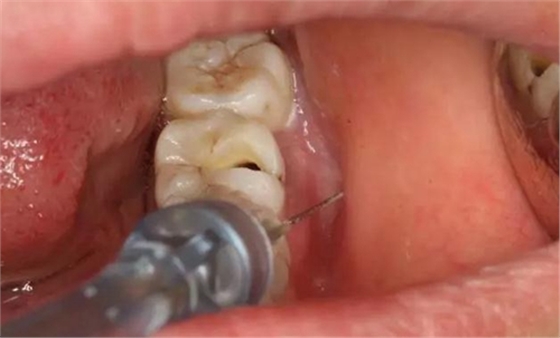

圖4.行下頜無痛阻滯麻醉。